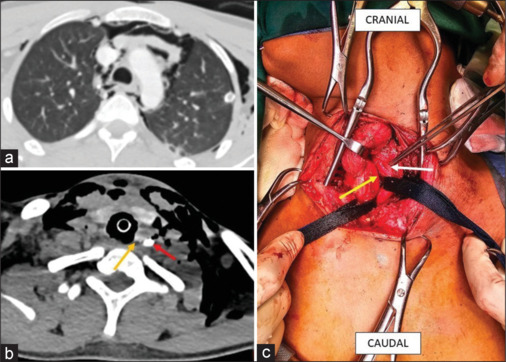

钝性创伤后食管损伤:诊断困境。

Esophageal Injury Following Blunt Trauma: A Diagnostic Dilemma.